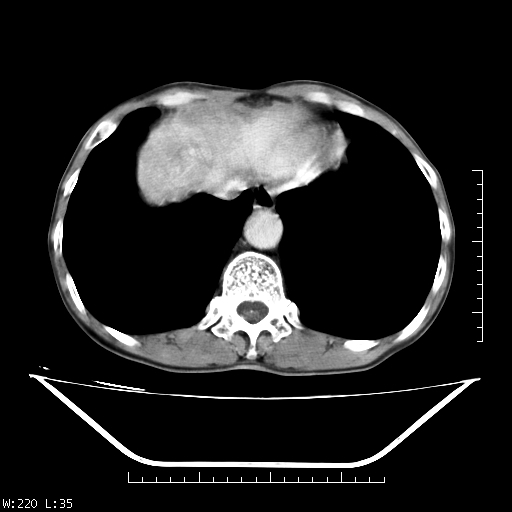

男,70,右上腹痛两月,有乙肝病史,b超提示肝占位,ct如下,请会诊。

补充:该患者afp9.24

肝右叶类圆型密度减低影,密度不均,边界清晰其内可见更低密度影,腹膜后可见小淋巴结肿大,增强扫描动脉期病灶明显强化,静脉期及延时扫描见强化不明显,快进快出表现。

1.肝右叶低密度影考虑为肝癌;

2.肝转移待除外。

平扫呈低密度占位,动脉期斑片状明显强化,病灶边缘清晰,见假包膜;门脉期呈低密度,符合肝癌快进快出强化特征

补充:该患者afp 9.24,似乎与原发性肝癌不符合,另胰头区结构正常吗?请大家继续发表高见。